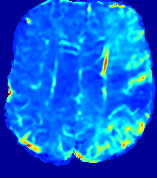

4.3.2 Diffusion Imaging via Advection-Diffusion

Slice #1Slice #2Slice #3Slice #4Slice #5Slice #6Dgtsuperscript𝐷gtD^{\text{gt}}Refer to captionRefer to captionRefer to captionRefer to captionRefer to captionRefer to captionDestsuperscript𝐷estD^{\text{est}}Refer to captionRefer to captionRefer to captionRefer to captionRefer to captionRefer to captionRefer to caption0.300.300.300.240.240.240.180.180.180.120.120.120.060.060.060.000.000.00(mm2/s)𝑚superscript𝑚2𝑠(mm^{2}/s)𝐕est𝟐subscriptnormsuperscript𝐕est2\|\bf{V}^{\text{est}}\|_{2}Refer to captionRefer to captionRefer to captionRefer to captionRefer to captionRefer to captionRefer to caption0.00300.00300.00300.00240.00240.00240.00180.00180.00180.00120.00120.00120.00060.00060.00060.00000.00000.0000(mm/s)𝑚𝑚𝑠(mm/s)

Figure 15: PIANO identifiability testing: diffusion imaging via advection-diffusion. Top row shows Dgtsuperscript𝐷gtD^{\text{gt}} used for simulating ground truth pure diffusion. Rows below show the estimated Destsuperscript𝐷estD^{\text{est}} and 𝐕est2subscriptnormsuperscript𝐕est2\|{\bf{V}}^{\text{est}}\|_{2} on corresponding slices. Note that the plotted value scale for 𝐕est2subscriptnormsuperscript𝐕est2\|{\bf{V}}^{\text{est}}\|_{2} is 0.01 of that for Dgtsuperscript𝐷gtD^{\text{gt}} and Destsuperscript𝐷estD^{\text{est}}.

Similarly, we test the behavior of PIANO when estimating both advection and diffusion from a pure diffusion-driven process. The goal is to determine if PIANO is able to recognize that there is only diffusion governing the given concentration time-series. We use the same ‘Diffusion Imaging’ data simulation of Sec. 4.2.1 as the concentration dataset, PIANO estimates both velocity 𝐕estsuperscript𝐕est{\bf{V}}^{\text{est}} and diffusivity Destsuperscript𝐷estD^{\text{est}}. Estimation results in Fig. 15 confirm PIANO’s identifiability again: the estimated 𝐕est2subscriptnormsuperscript𝐕est2\|{\bf{V}}^{\text{est}}\|_{2} is almost invisible compared to Destsuperscript𝐷estD^{\text{est}}, even plotted with a 1%percent11\% value range compared to that for Destsuperscript𝐷estD^{\text{est}}. On the other hand, Destsuperscript𝐷estD^{\text{est}} achieves comparable estimation performance as ‘Diffusion Imaging via Diffusion’ in which PIANO predicts Destsuperscript𝐷estD^{\text{est}} alone (shown in Fig. 13).